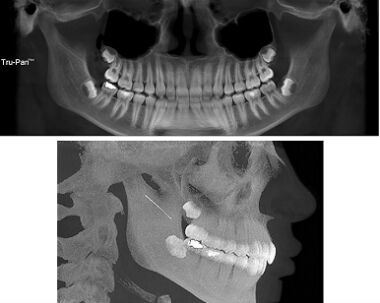

18.右側下顎第一大臼齒接受植牙治療,於牙冠黏著固定3個月後,追蹤檢查無咬合異常,但植牙區明顯有牙齦出血及流膿,檢測囊袋深度>5 mm,根尖X光片如圖所示。造成其植體周圍炎最可能的原因為何? (A)不當咬合力 (B)假牙邊緣不密合 (C)黏著劑殘留 (D)後牙向前傾斜分力